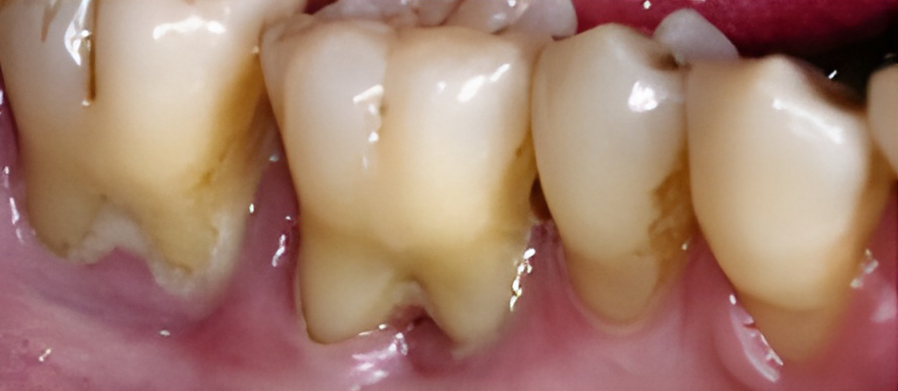

치은염을 치료하지 않고 방치하면 플라그가 뿌리로 퍼져 뼈와 연조직에 감염과 손상을 일으킬 수 있습니다. 잇몸이 치아에서 분리되어 물러나기 시작할 수 있으며 잇몸 라인 아래에 주머니가 생겨 플라크와 음식물이 쌓일 수 있습니다.

잇몸이 심하게 붓고 피가 자주 나며 치가가 흔들리기도 합니다. 치아 뿌리가 드러나기도 하며 때로는 잇몸에 고름이 나와 음식물을 잘 씹을 수가 없습니다.

잇몸에 고름이 차 있다면 배농이 필요하고, 잇몸을 절개해서 염증조직을 제거하거나 치은이나 뼈를 이식하는 수술을 시행하기도 합니다.